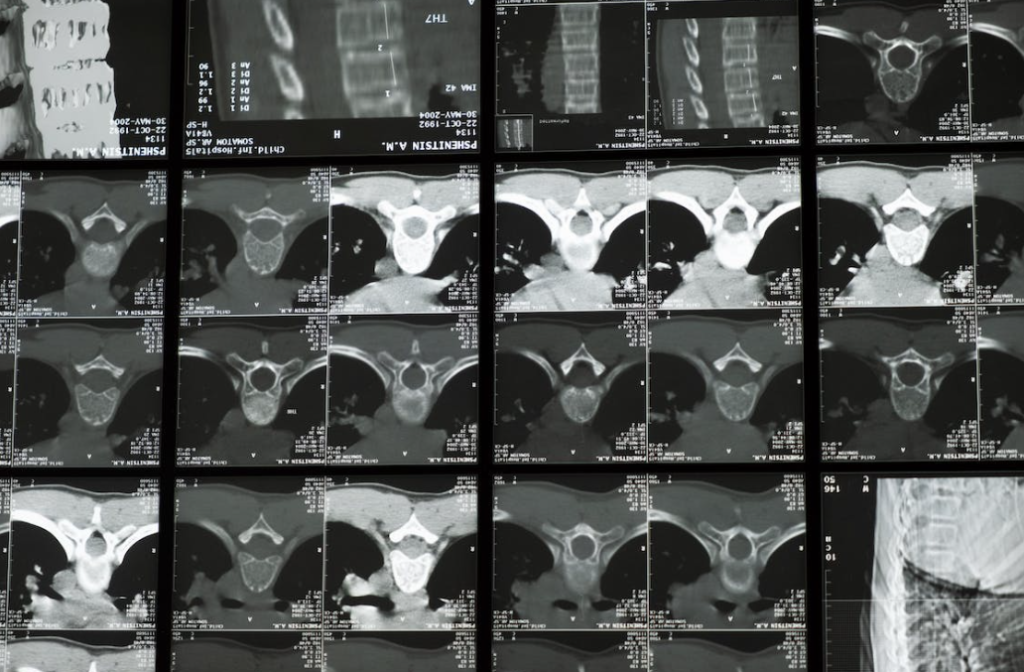

Dijagnoza i liječenje: Dijagnoza spondiloze vratne kralježnice obično se postavlja temeljem medicinske povijesti, fizikalnog pregleda i radioloških pretraga kao što su rendgenske snimke, magnetska rezonanca (MRI) ili kompjutorska tomografija (CT).

- Dijagnoza i liječenje: Dijagnoza spondiloze lumbalne kralježnice obično se postavlja temeljem medicinske povijesti, fizikalnog pregleda i radioloških pretraga kao što su rendgenske snimke, magnetska rezonanca (MRI) ili kompjutorska tomografija (CT). Liječenje može uključivati konzervativne metode poput fizikalne terapije, lijekova protiv bolova, injekcija ili kirurškog zahvata u težim slučajevima.

Dijagnoza i liječenje: Dijagnoza spondiloze torakalne kralježnice obično se postavlja temeljem medicinske povijesti, fizikalnog pregleda i radioloških pretraga kao što su rendgenske snimke, magnetska rezonanca (MRI) ili kompjutorska tomografija (CT). Liječenje može uključivati konzervativne metode poput fizikalne terapije, lijekova protiv bolova ili injekcija, a u težim slučajevima može se razmotriti kirurško liječenje.

- Radiološke pretrage: Uključujući rendgenske snimke, magnetsku rezonancu (MRI) i kompjutorsku tomografiju (CT) radi preciznog prikaza kralježnice i degenerativnih promjena.